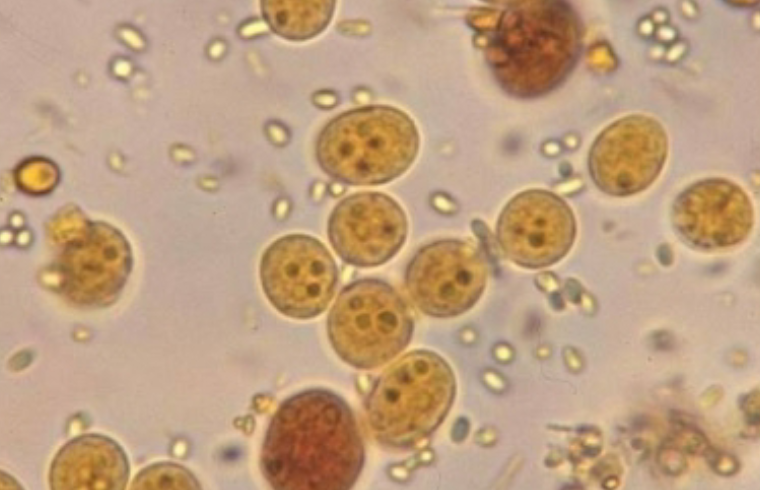

Entamoeba coli (cyst)

Entamoeba coli (cyst)